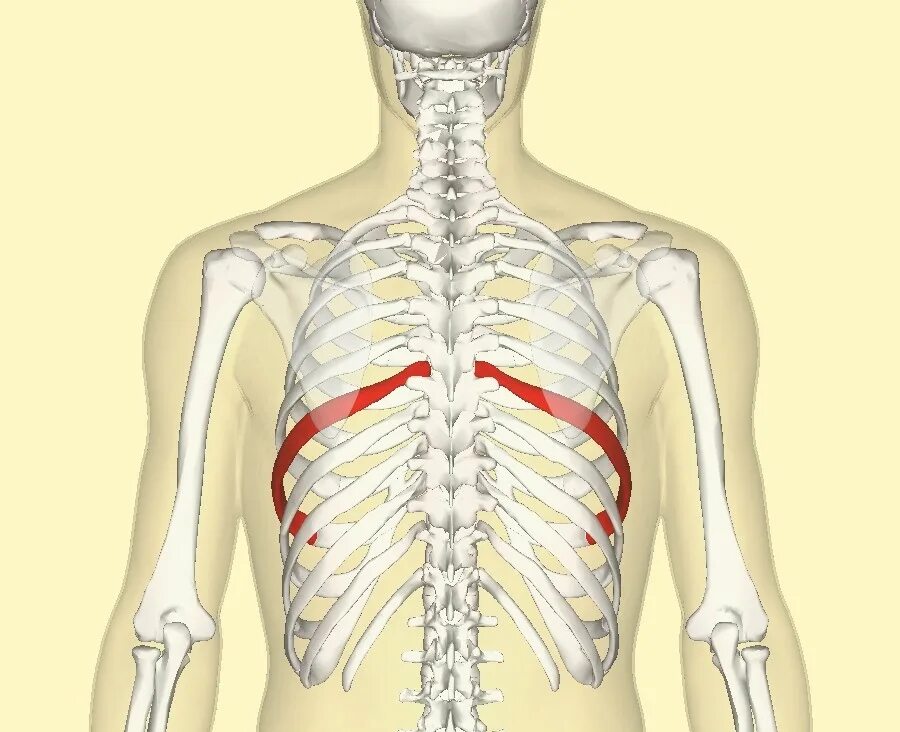

Множественные ребра